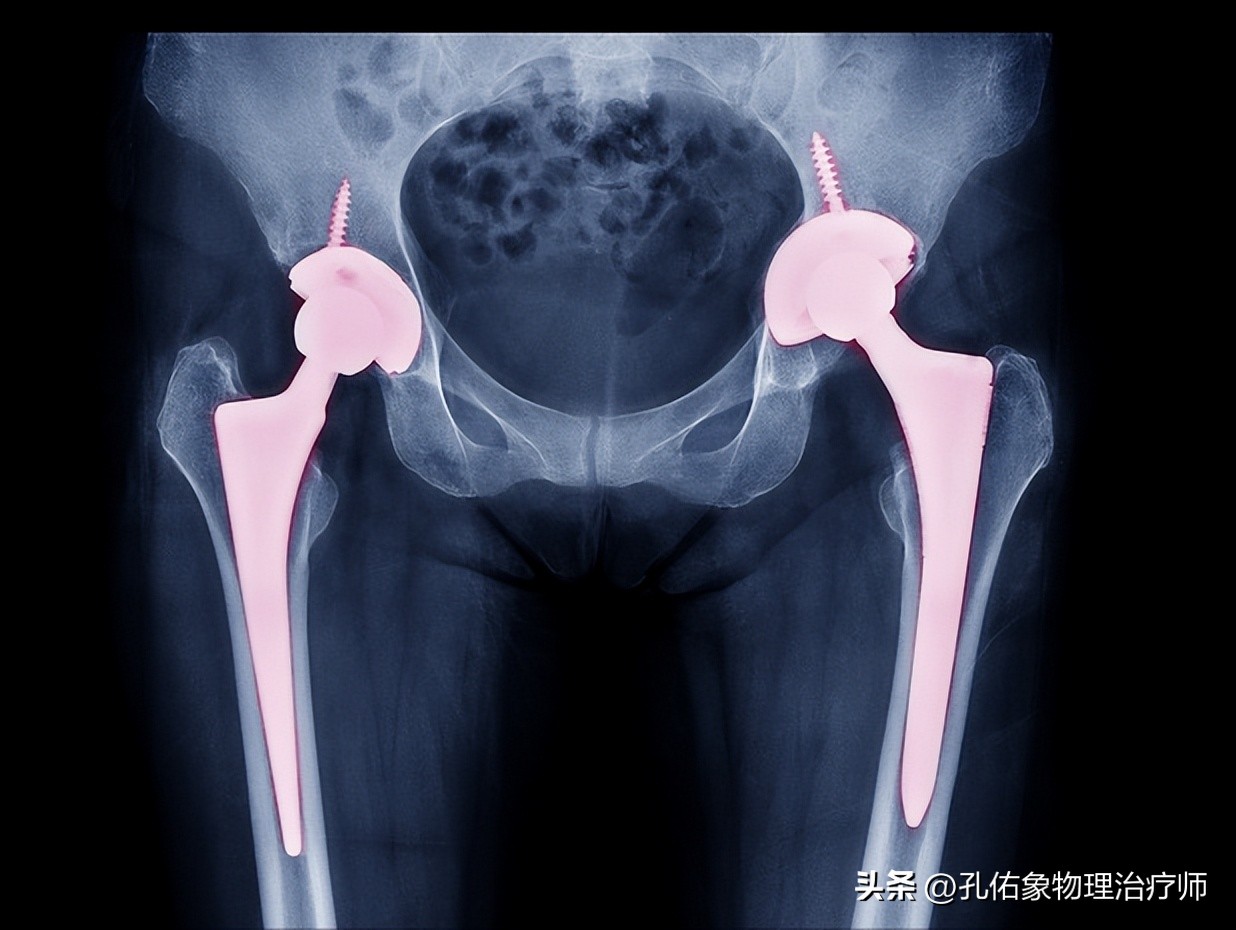

医生告知她,需要做手术了,并且要置换关节,没法再保守继续使用了;罗女士纳闷了,年纪轻轻的,怎么一个胯部疼痛就坏死了呢?

如上图所示,第一张是正常的,在关节的骨头表面有血管支配,倘若骨头表面的血液供应受到某种原因影响,骨头表面缺血,部分骨细胞就会凋亡,逐渐出现骨坏死,发生骨头塌陷、形变而没法完成它的承重及活动功能。